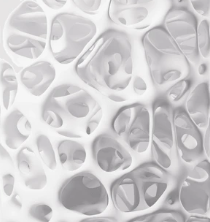

The Premium Screening is Executive Health’s most extensive medical examination - offering a full overview of your health in just one visit.Through high-resolution MRI imaging, advanced laboratory analysis and specialist consultation, we detect potential risks before symptoms appear. Our experienced physicians provide clear answers and personal guidance, helping you stay healthy, informed and in control.